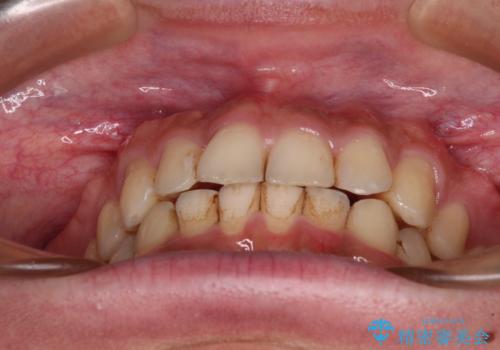

前歯のデコボコをスッキリ改善 インビザライン矯正

- 上下前歯のデコボコを気にして来院された患者様です。

全体的に叢生は軽度であったため、インビザラインにて矯正治療を行うこととしました。

デコボコの改善はもちろん、下顎前歯が隠れてしまうディープバイトも一緒に改善することができ、奥歯への負担を軽減することができました。